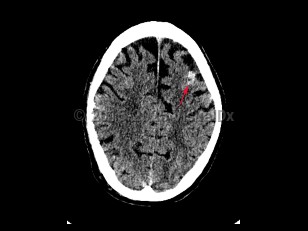

Subarachnoid hemorrhage (SAH) is bleeding directly into the cerebrospinal fluid (CSF) within the subarachnoid space that surrounds the brain. It usually presents as a severe sudden-onset headache, often described as the worst headache of the patient's life, with radiation of pain down the neck and back. Onset of headache may be accompanied by a brief loss of consciousness, nausea, vomiting, and meningismus. SAH occurs in about 10 per 100 000 people per year. Incidence increases with age and peaks in the sixth decade of life. Risk factors include female sex, smoking, alcohol use, drug abuse, hypertension, oral contraceptive use, known cerebral vascular malformation, collagen vascular disease, and family history of SAH. In the United States, African Americans are at higher risk.

Cerebral aneurysms > 5-7 mm are most likely to rupture. Approximately 1%-3% of patients visiting the emergency department for a headache are subsequently found to have a SAH. Trauma is the most common cause of SAH; however, nontraumatic SAH is found to result from a ruptured saccular aneurysm in 80% of cases. Patients with SAH require close monitoring and often require intensive care unit admission.

Subarachnoid hemorrhage